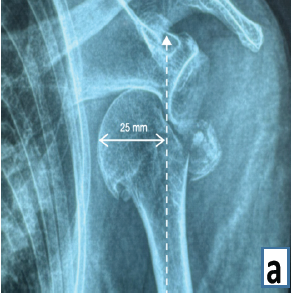

Extraarticular Interfragmentary Fixation of an Irreducible Pipkin Type 1 Fracture Dislocation of the Hip – A Case Report

Dinesh Kale , Sahil Kale , Sanjay Pratheep , Ajit Modak , Ravindra Bharamgunde , Sachin Kale

………………………………p.194-198